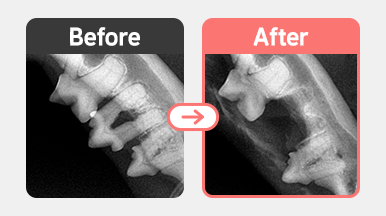

[발치 사례] 코숏 / 6살 / 치주염 PD4 M3

진단명 : PD4 M3

같은 환자의 반대쪽 치아에서 PD4 + M3(동요도 3단계)가 확인되었으며,

뼈 소실이 진행된 상태로 판단되어 예후를 고려한 발치를 결정하였습니다.

코숏 6살 고양이의 PD4 M3 치주염 발치 수술 전후 사진, 잇몸뼈 소실과 동요도 3단계 치아 확인 후 발치 진행